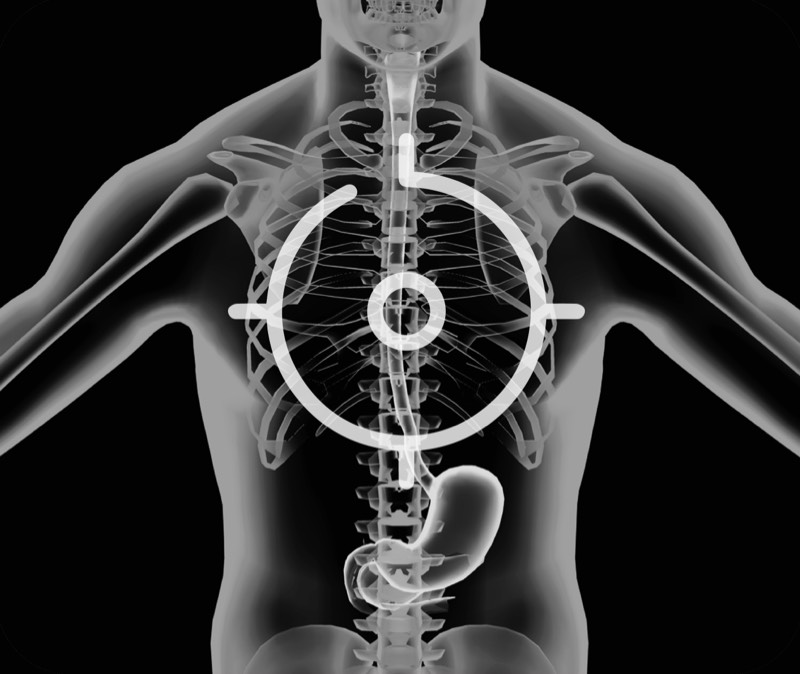

食管内间质瘤清晰显像